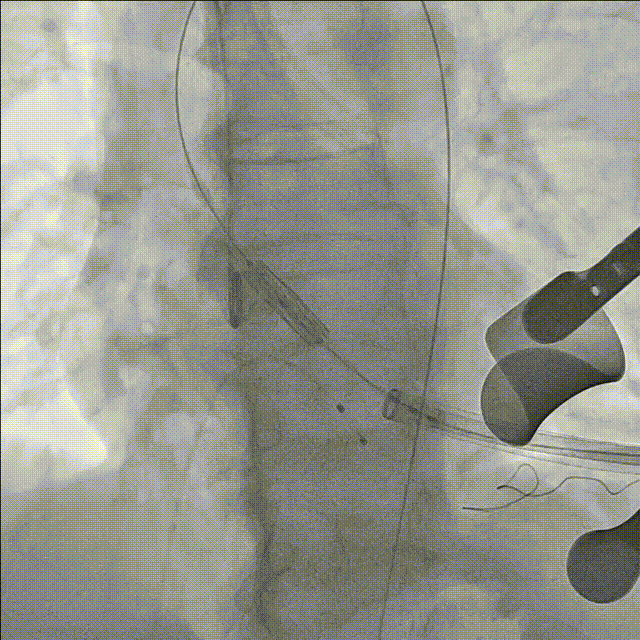

显露心尖,于心尖预置双层3-0Prolene带垫片荷包,穿刺心尖,进入造影导丝及鞘管,经导丝将单弯导管送至降主动脉,交换支撑导丝至降主动脉。

沿超硬导丝送入预装好的26mm SAPIEN 3瓣膜,经心尖进入左心室,跨过主动脉瓣置于主动脉瓣上

瓣膜定位